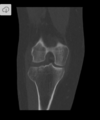

Fratura do platô tibial lateral - Schatzker tipo 2 (traço de fratura + depressão do plato lateral).